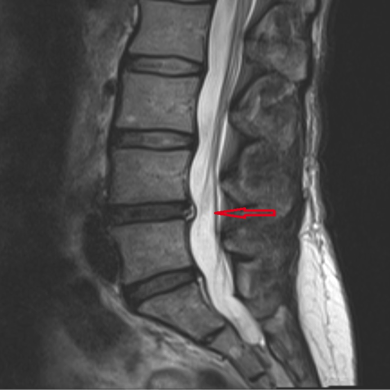

The inside of your disc doesn’t have any nerves, but the outer part of the annulus fibrosis does. When the disc is damaged or starts to deteriorate, it can expose those nerves, which can become irritated thanks to the inner jelly-like core leaking out. This can result in extremely painful symptoms for the patient.

- Deterioration of the outer part of your discs, leading to the inner material leaking out or even for the disc to rupture.